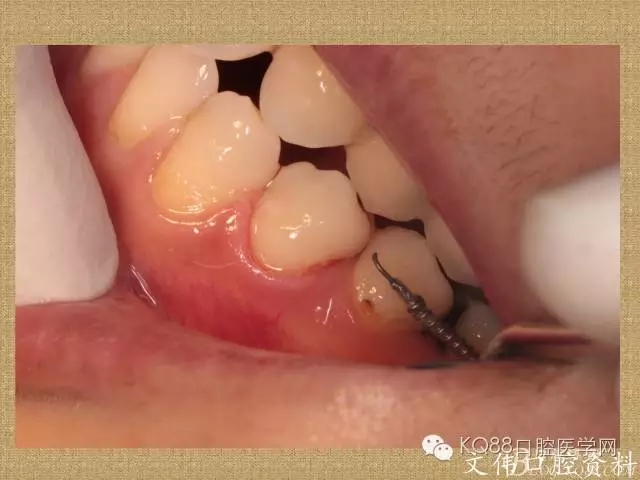

楔狀缺損的樹脂充填